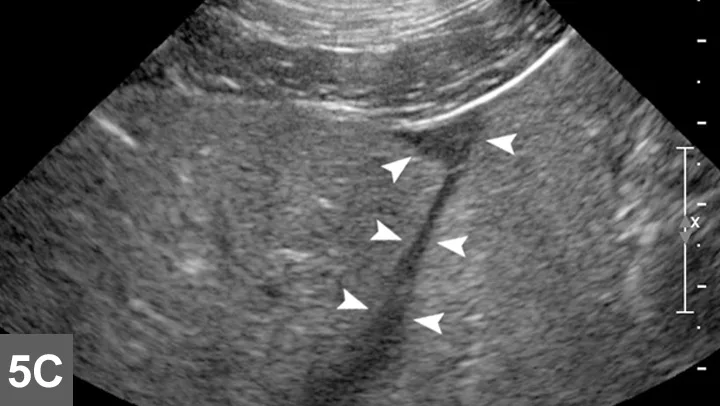

Biopsy needle tract within the patient after firing and just before removing the biopsy device (B). Post-biopsy hemorrhage often collects between hepatic lobes as seen in this image (white arrow heads) (C). The echogenic fluid represents acute hemorrhage. Color flow Doppler post-biopsy ensures there is no persistent hemorrhage in the peritoneal space (D). Power Doppler imaging is the most sensitive form of Doppler to detect the presence or absence of blood flow.

Step 8: Inspect for Hemorrhage

Every time a biopsy is made, the site should be inspected for evidence of hemorrhage. Hemorrhage will often collect around and between liver lobes as seen in 5C between the arrowheads. Color (or power) Doppler ultrasound may help visualize active bleeding as seen in 5D. Once the patient is no longer bleeding, the patient can be recovered. Observe the patient closely in the postoperative period for clinical evidence of blood loss. Serial ultrasound examinations may be beneficial for discovering progression hemorrhage. If the patient continues to bleed, a blood transfusion may be needed. It is usually beneficial to obtain packed-cell volume readings at 15 and 45 minutes post-biopsy to ensure that active bleeding has stopped. An external elastic belly wrap can be helpful in preventing further hemorrhage.